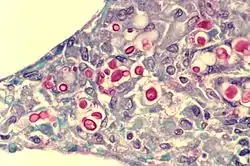

![]() Filobasidiella neoformans в легенях пацієнта на СНІД. Капсула дріжджів забарвлена червоним. | ||||||||||||||||||||

Filobasidiella neoformans — (телеоморф, також відома під своєю анаморфною назвою Cryptococcus neoformans) — вид інкапсульованих дріжджеподібних грибів, що може жити в тілі як тварин, так і рослин. Цей вид належить до відділу базидіоміцетів. F. neoformans зазвичай росте як дріжджі (тобто одноклітинний організм) і розмножується за допомгою брунькування. За певними умовами, як в природі, так і в лабораторії, F. neoformans може формувати гіфи і рости як волокнистий грибок[1]. Під час росту у формі дріжджів, F. neoformans формує помітну капсулу, сформовану здебільшого з полісахаридів, яка може бути легко візуалізована за допомогою туші. Частинки пігменту не проникають до капсули, ака оточує сферичні дріжджові клітини, приводячи утворення зони очищення або «ореолу» навколо клітин.